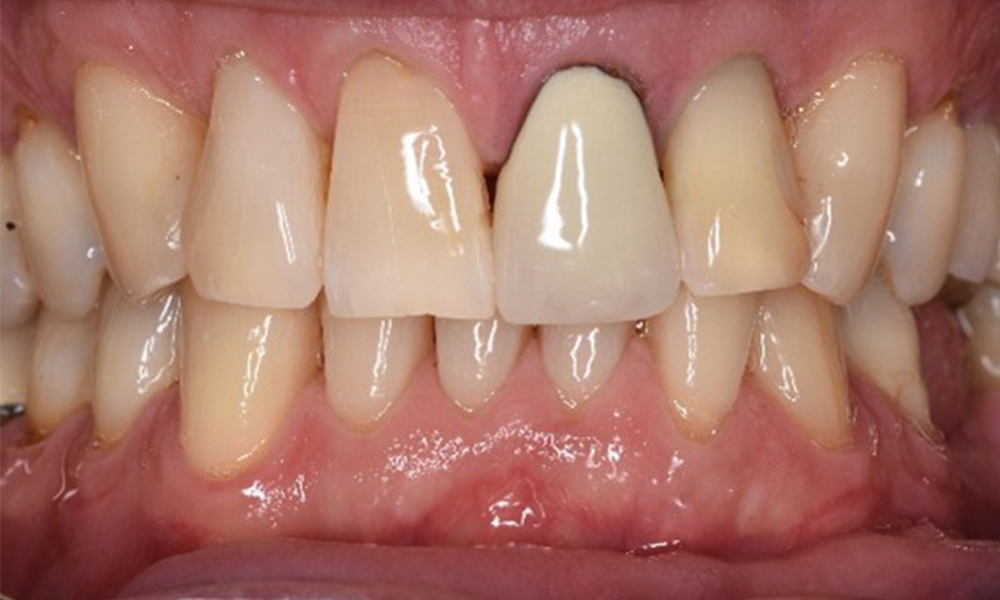

Der (mund)-gesunde Patient mit Implantaten

Der 55-jährige Patient gibt in der Anamnese an, keine Allgemeinerkrankungen zu haben und keine Medikamente einzunehmen. Die Lebensgewohnheiten des Patienten sind ebenfalls unauffällig. Der Patient hat einige zahnärztliche Restaurationen und zwei Implantate (2. und 4. Quadrant). Anhand der aktuellen Befunde lässt sich eine Gingivitis bei stabilem parodontalen Zustand am reduzierten Parodont (Stadium III, Grad A) feststellen. mehr Infos